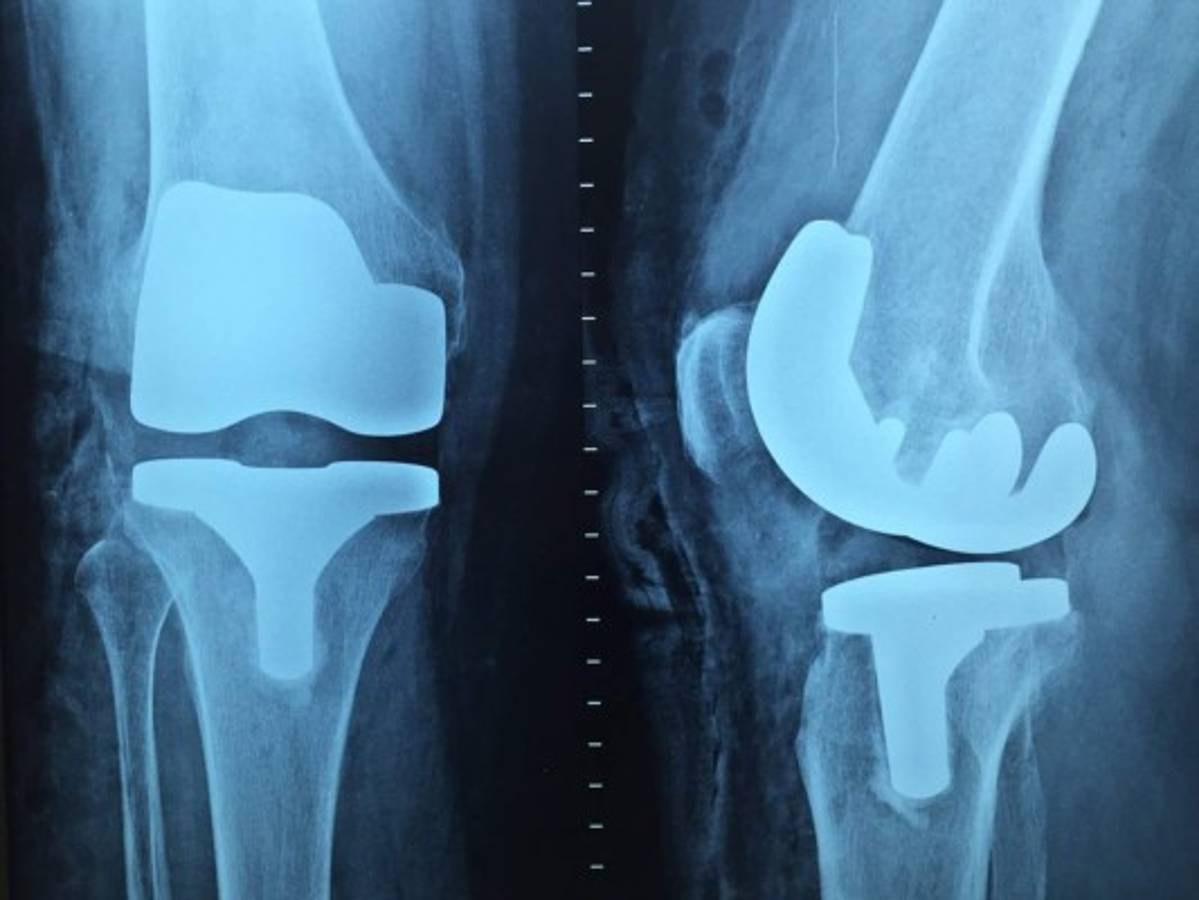

El investigador responsable de este nuevo tratamiento, José Pérez, explicó, “la tecnología AVS puede ser adaptada de manera sencilla a los procedimientos actualmente empleados para la producción de los biomateriales metálicos”. Estos son imprescindibles en prótesis sometidas a esfuerzos elevados como son las de cadera y rodilla.